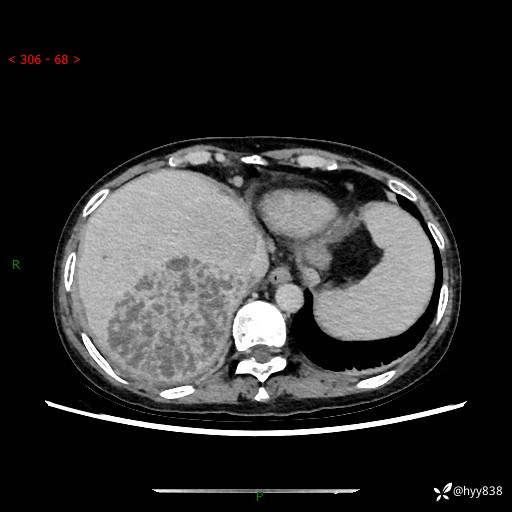

上腹部CT平扫